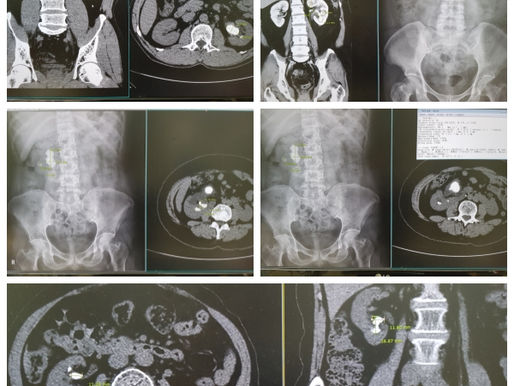

Neglected DJ catheter

A 74-year-old female patient. She underwent LT Mini-PCNL on Oct. 5, 2015. She did not visit my hospital postoperatively even though she...